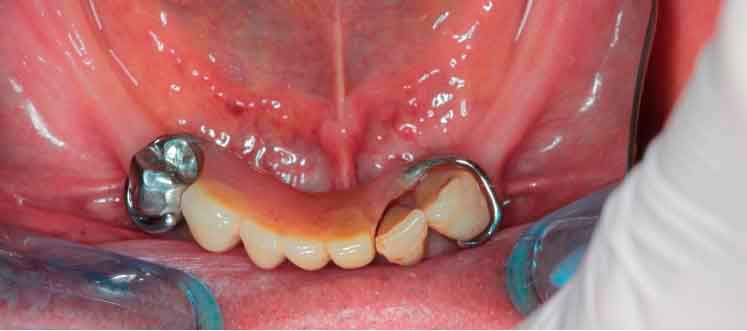

Dans un flux de travail numérique , la première étape implique l'acquisition par scanner intra-oral (IOS). Cependant, dans les cas où les références sont insuffisantes, obtenir une empreinte précise peut être difficile. Découvrez une méthode alternative pour construire votre patient virtuels dynamique

Modèles 3D - Occlusion obtenue par la caméra intra-orale

Lorsque les scans IOS traditionnels manquent de références nécessaires, les données du CBCT peuvent servir d'alternative viable. En utilisant les fichiers du CBCT, le clinicien peut établir des références anatomiques précises pour la planification du traitement.